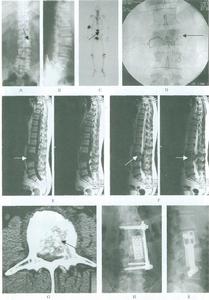

分期4、前列腺腫瘤的其他影像學檢查計算機斷層掃描(CT)檢查:對DRE和TRUS檢查懷疑前列腺癌的病人應進行前列腺CT檢查。盆腔其他部分的CT可採用10mm層厚掃描,而前列腺的CT則套用5mm層厚連續掃描,且應做靜脈增強CT檢查以增加病變與正常組織的對比。由於CT檢查不能顯示正常前列腺的三個帶(外周帶、中央帶和移行帶),加之多數腫瘤組織的X線密度與正常腺體近似或相同,因此CT對於早期前列腺癌的診斷敏感性明顯低於磁共振(MRI)。對於腫瘤鄰近組織和器官的侵犯及盆腔內轉移性淋巴結腫大,CT的診斷敏感性與MRI相近。所以前列腺癌患者進行CT檢查的目的主要是協助臨床醫師進行腫瘤的臨床分期,不能用於前列腺癌的普查。前列腺癌的主要CT表現為增強掃描時癌灶呈現增強不明顯的低密度區,被膜顯示不規則。尤其當癌腫突破前列腺被膜後,外形明顯不規則,腺體周圍脂肪消失,精囊受侵犯後可表現出精囊境界模糊,膀胱精囊角消失或精囊增大;當腫瘤侵犯膀胱或前列腺周圍器官時盆腔CT均可表現出相應的改變,當盆腔淋巴結有腫瘤轉移後,CT可以根據盆腔淋巴結群大小的改變,判斷有無轉移發生。

臨床分期5、磁共振(MRI)掃描:磁共振有很好的軟組織解析度,能直接多方向平面(三維)成像,並可選擇不同的掃描參數和序列成像,因此,MRI對前列腺的檢查優於其他影像學方法。前列腺的MRI檢查一般採用SE(自旋迴波)序列。成年人正常的前列腺T2加權圖像上可以顯示出前列腺三部分結構——前肌纖維基質部、中央帶(包括移行帶)和外周帶。前列腺癌的MRI檢查主要先用T2加權序列,在T2加權像上,如高信號的前列腺外周帶出現低信號的缺損區,如前列腺帶狀結構破壞,外周帶與中央帶界限消失時應考慮前列腺癌的可能。而T1加權像上腫瘤信號均勻,與正常前列腺部分的信號難以區別。另外MRI檢查可以顯示前列腺包膜的完整性、是否侵犯前列腺周圍組織及器官,如精囊、膀胱、直腸等,MRI還可以顯示盆腔淋巴結受侵犯的情況及骨轉移的病灶。但是MRI檢查對前列腺癌的診斷也存在一定的局限性,在鑑別前列腺癌及伴鈣化的前列腺炎、較大的良性前列腺增生、前列腺瘢痕、結核等病變時常無法明確診斷。因此,影像學檢查TRUS、CT和MRI等在前列腺癌的診斷方面都存在局限性,最終明確診斷還需要前列腺細針穿刺活檢取得組織學診斷。

7、前列腺癌的核素檢查(ECT):前列腺癌的最常見遠處轉移部位是骨轉移,早期骨轉移多不表現出骨痛症狀,X線檢查對診斷骨轉移病灶並不敏感。目前人們多採用同位素核素全身骨骨像技術檢查前列腺癌懷疑有遠處轉移的患者以早期發現轉移病灶。靜脈注入99mTc-亞甲基二磷酸鹽(MDP)後,2小時內約50%被骨骼的主要無機鹽成分——羥基磷灰石晶體吸附和未成熟的骨膠原結合,用核素顯像儀(γ-相機)照相後可顯示出人體內的放射性影像。99mTc-MDP在骨內的聚集量與局部成骨活躍程度和血液量呈正比,因此正常骨骼的乾骺端和扁平骨影像較濃,有成骨和修復過程的骨病變,以及局部充血的骨病變也可以提高局部。99mTc-MDP濃集顯影。而骨轉移灶多為血行播散而來,病灶常為多發且隨機分布,轉移瘤破壞骨質,多伴有局部修復成骨過程,故表現為放射性濃集。核素全身骨顯像技術可比常規X線片提前3-6個月發現骨轉移灶,是診斷骨轉移瘤最靈敏和最簡便的方法。回顧性研究結果顯示前列腺癌臨床分期Ⅰ期患者發現骨轉移者為7%,Ⅱ期患者15%陽性,Ⅲ期癌腫者25%陽性,Ⅳ期時陽性率為60%。因此,一旦前列腺癌診斷成立,不論臨床分期如何均應常規進行全身骨顯像檢查,這對於判斷前列腺癌準確臨床分期、選擇適當的治療方案、了解患者的預後都有著十分重要的意義。

當通過DRE檢查後懷疑患者已發生局部晚期癌或盆腔淋巴結廣泛浸潤、血清PSA水平大於20ng/ml、前列腺活檢示低分化癌腫(即Gleason評分大於7)時,應做CT和MRI檢查。雖然MRI本身並不能幫助確定局部晚期癌,有研究顯示其可以發現是否癌腫已包膜外侵犯生長或精囊已受侵犯。